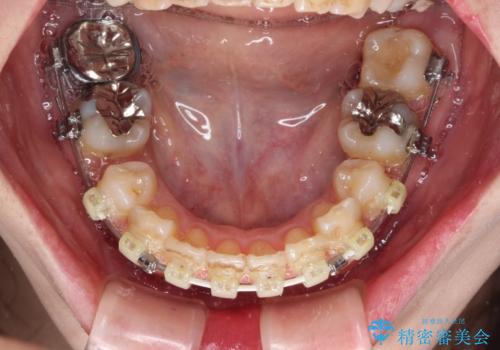

- ハーフリンガル

目立たない装置が希望であったため、上顎が裏側装置である、ハーフリンガル装置を選択されました。